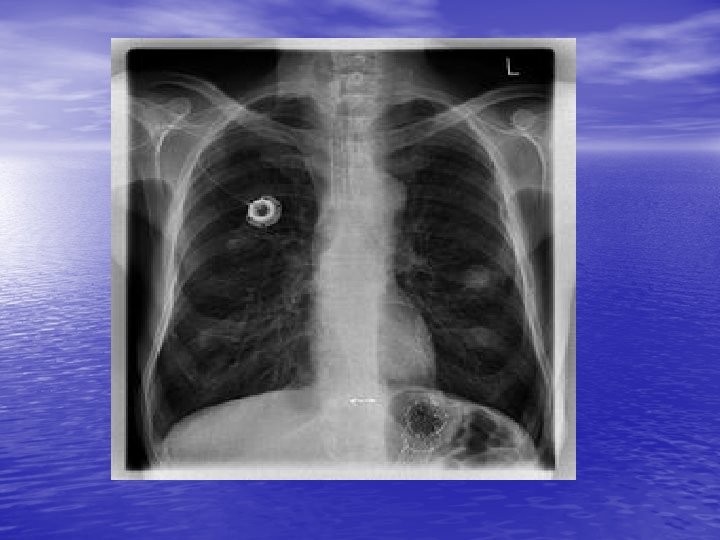

• Contrôle du bon positionnement du cathéter par radiographie per opératoire (en regard de la bifurcation bronchique) • Chambre mise en place le plus souvent en pré pectoral • Coté à discuter avec le patient (chasseur)